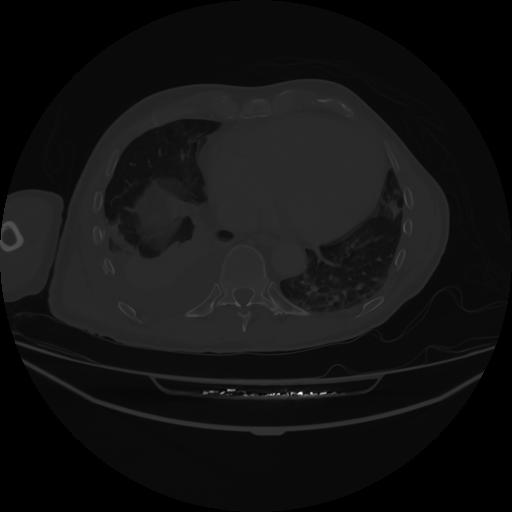

5 CUERPO,CE,Vol,1.0,CUERPO,,